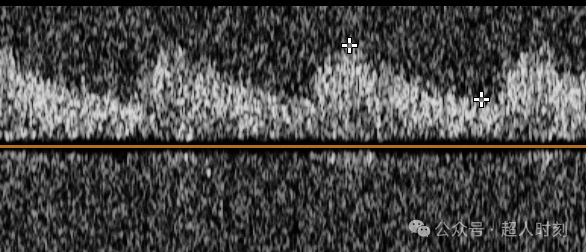

TCCD(图3)不仅能够得到TCD那样的频谱图,还能直观看到血管的走行和血流的状态,是可视化医学的一个明显特征。

图3a

图3b

图3c